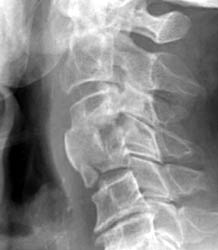

76 y.o male with symptoms of myelopathy, underwent C3,4 ACDF. 1 month later the patient had complaints of severe dysphagia, feelings of  'food and liquid getting caught'.

Latera C-spine - Click on the image to enlarge This radiograph take 1 month later demonstrates anterior extrusion of bone graft material at C3-4 and an endplate fracture at C4.